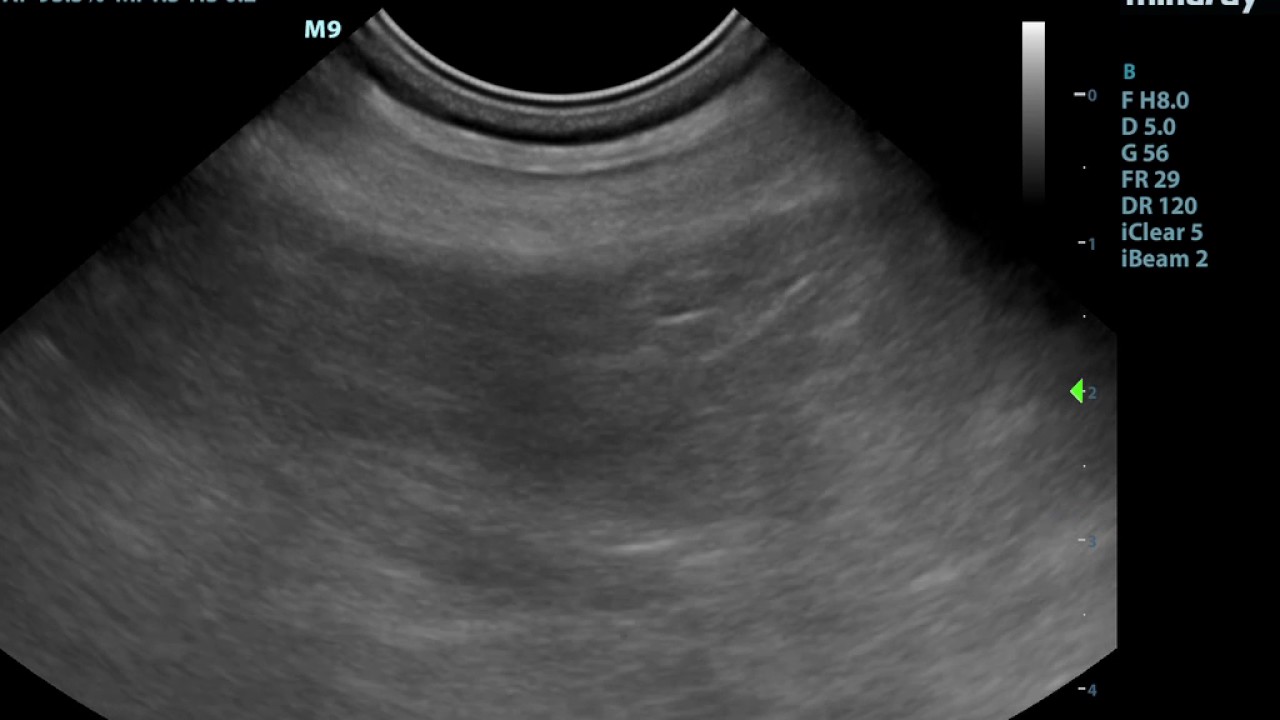

Abdominal Ultrasound Anatomy Small Animal Ultrasonogr vrogue.co Small Animal Ultrasound.com To access the references, click on the references tab above. Welcome to the companion website for. This online course is a preliminary to the atlas of. The references are open access and no log in or registration is required. 1m+ visitors in the past month Learn, exchange and collaborate on small animal ultrasonography with this website and its companion book.. Small Animal Ultrasound.com.